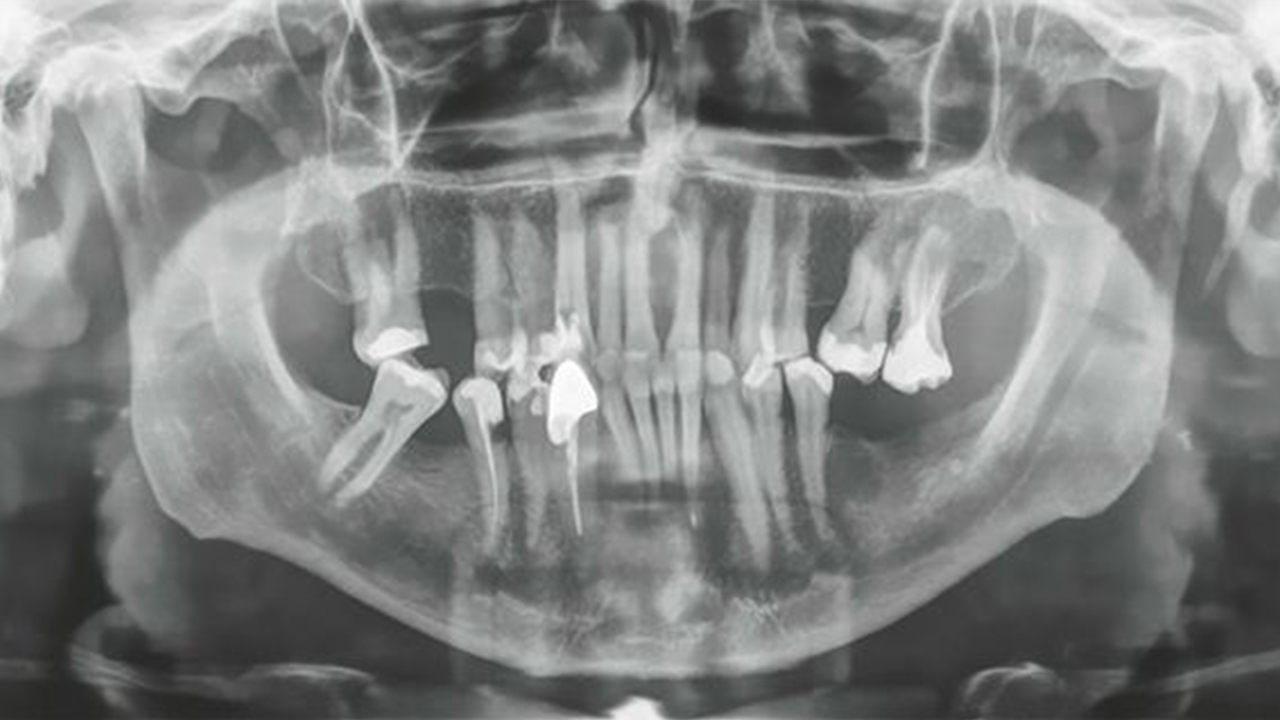

حصل رجل من كرواتيا على رقم قياسي في موسوعة غينيس لامتلاكه أطول سن بشري، بقياس 1.46 بوصة مايعادل 3.72 سم.

وأصيب طبيبه بالصدمة من طول السن، ووصف سنه بأنه "غير معقول" بعد أن كشفت الأشعة السينية عن طوله المدهش.

وأكدت الآن غينيس للأرقام القياسية أن الرجل يمتلك أطول سن بشري مستخرج يبلغ طوله 3.72 سم (1.46 بوصة).